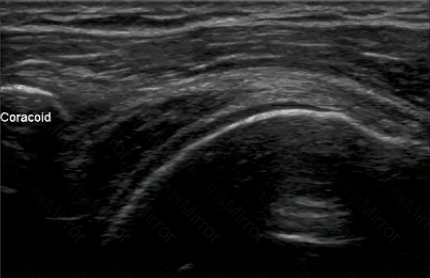

What is the position of the arm MOST likely used to obtain this B-Mode image of the shoulder?